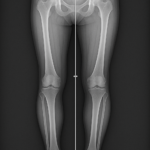

La radiographie est l’examen de référence pour visualiser le gril costal. Elle permet de :

- Détecter fractures, fissures, anomalies osseuses.

- Identifier des lésions tumorales ou inflammatoires.

- Évaluer la morphologie du gril costal et rechercher des déformations.

Elle est souvent incluse dans une radiographie thoracique standard, qui étudie aussi les poumons et le cœur.